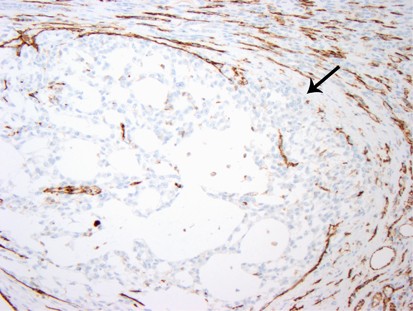

Tumor in this arcuate vein has begun to focally invade through the wall (arrow) obliterating the endothelial cell lining. CD31 stain.